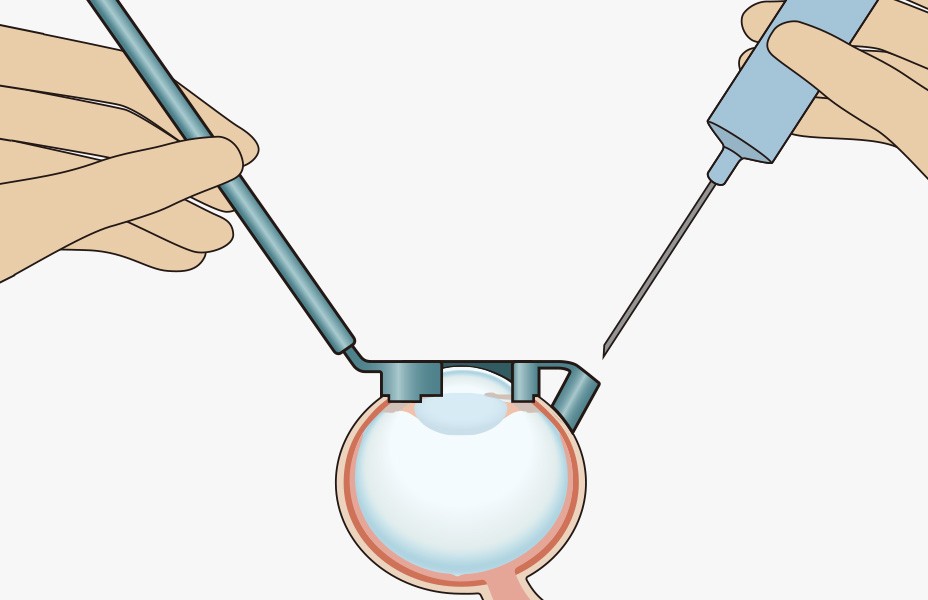

手順3:注射筒より手を離す

■注射筒はガイドにより固定されているので、注射筒から手を離して他の操作をすることができます。